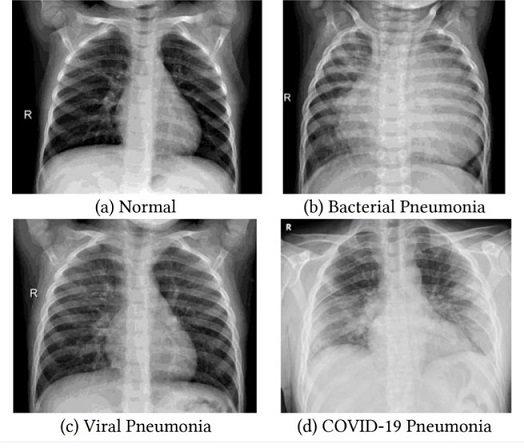

ลักษณะภาพจากการ X-Ray

ภาพจาก X-Ray จะบ่งบอกปริมาณการดูดซับรังสีเอ็กซ์ที่แตกต่างกัน ขึ้นอยู่กับความหนาแน่นของสสาร โดยธาตุน้ำหนักเบาจะยอมให้รังสีผ่านไปได้มาก ในขณะที่ธาตุหนักจะดูดซับรังสีไว้

เช่น แคลเซียมในกระดูกสามารถดูดซับรังสีเอกซ์ได้มากที่สุด จึงทำให้มองเห็นภาพเอกซเรย์กระดูกเป็นสีขาว

ส่วนคาร์บอน ไฮโดรเจน และไนโตรเจน ในเนื้อเยื่อและอวัยวะภายใน จะดูดซับรังสีได้น้อยกว่าจึงมองเห็นภาพเป็นสีเทา

ในขณะที่ออกซิเจนดูดซับรังสีได้น้อยที่สุด จึงทำให้มองเห็นปอดเป็นสีดำ